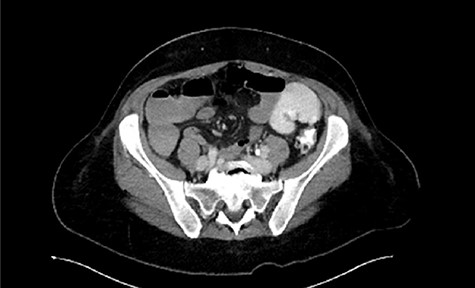

Immediate postoperative course was uneventful until postoperative day (POD)-5 when she experienced multiple watery stools, diffuse abdominal pain, fever (102.6F) and leukocytosis (23000/UL). Clostridium difficile infection was ruled out with a negative stool toxin assay. Her abdominal exam remained nonspecific until POD-6 when she had bilious emesis. A computed tomography (CT) scan revealed perforated diverticulitis with pelvic abscess and multiple colonic diverticulitis with an associated small bowel obstruction (SBO) (Images 1–4). No prior history of diverticulitis was reported.

Axial image of pelvic collection. U: uterus; *: pelvic abscess cavity; White arrows: rim-enhancing pelvic abscess cavity.